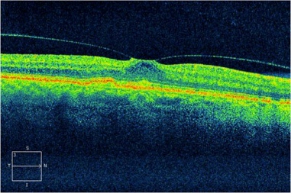

(OCT检查显示后葡萄膜炎患者的黄斑前膜,其中纤维膜在黄斑表面产生牵拉的力量,可引致黄斑水肿或裂孔,引致视野中央出现暗点)